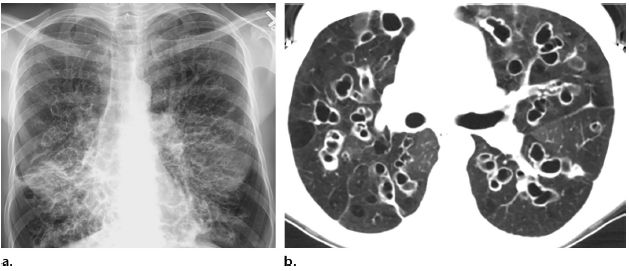

支氣管擴(kuò)張的診斷主要依據(jù)患者的病史、癥狀和體征,以及輔助檢查如高分辨率CT掃描等,醫(yī)生會(huì)根據(jù)患者的具體情況進(jìn)行綜合分析,以確定診斷。